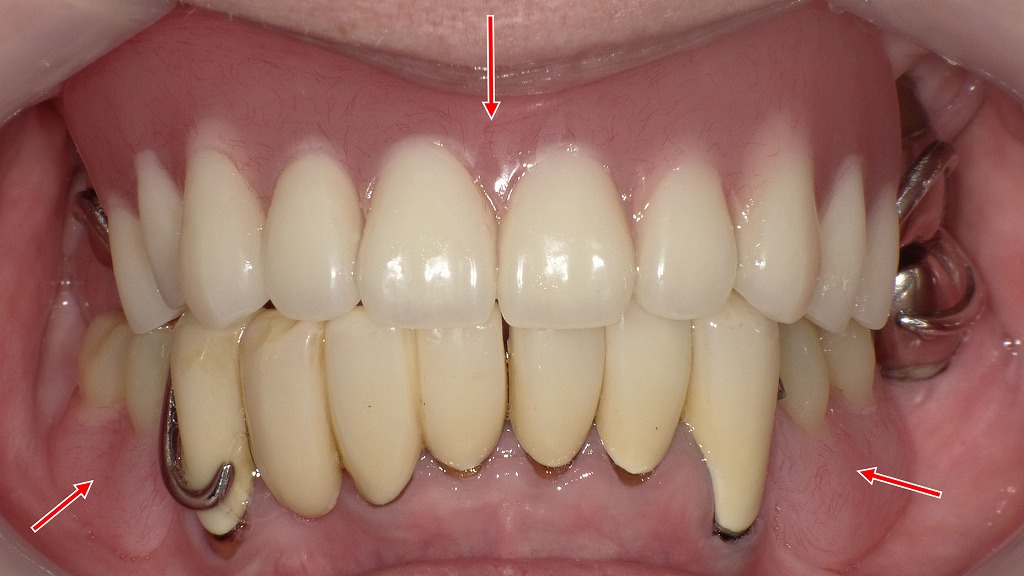

上下顎に保険適用のクラスプ義歯(部分入れ歯)を装着した症例です。

噛み合わせの高さや歯並び、義歯の安定性を細かく調整することで、見た目だけでなく「しっかり噛める」「違和感が少ない」入れ歯に仕上げています。

保険の入れ歯であっても、設計・調整・適合精度によって快適さは大きく変わります。入れ歯が合わない、痛い、噛みにくいと感じている方は、適切な診断と調整が重要です。